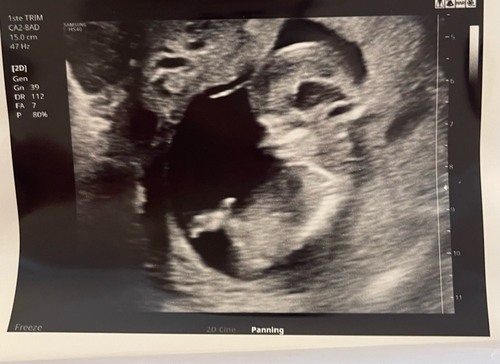

Nou iemand een idee🫣

Meisje